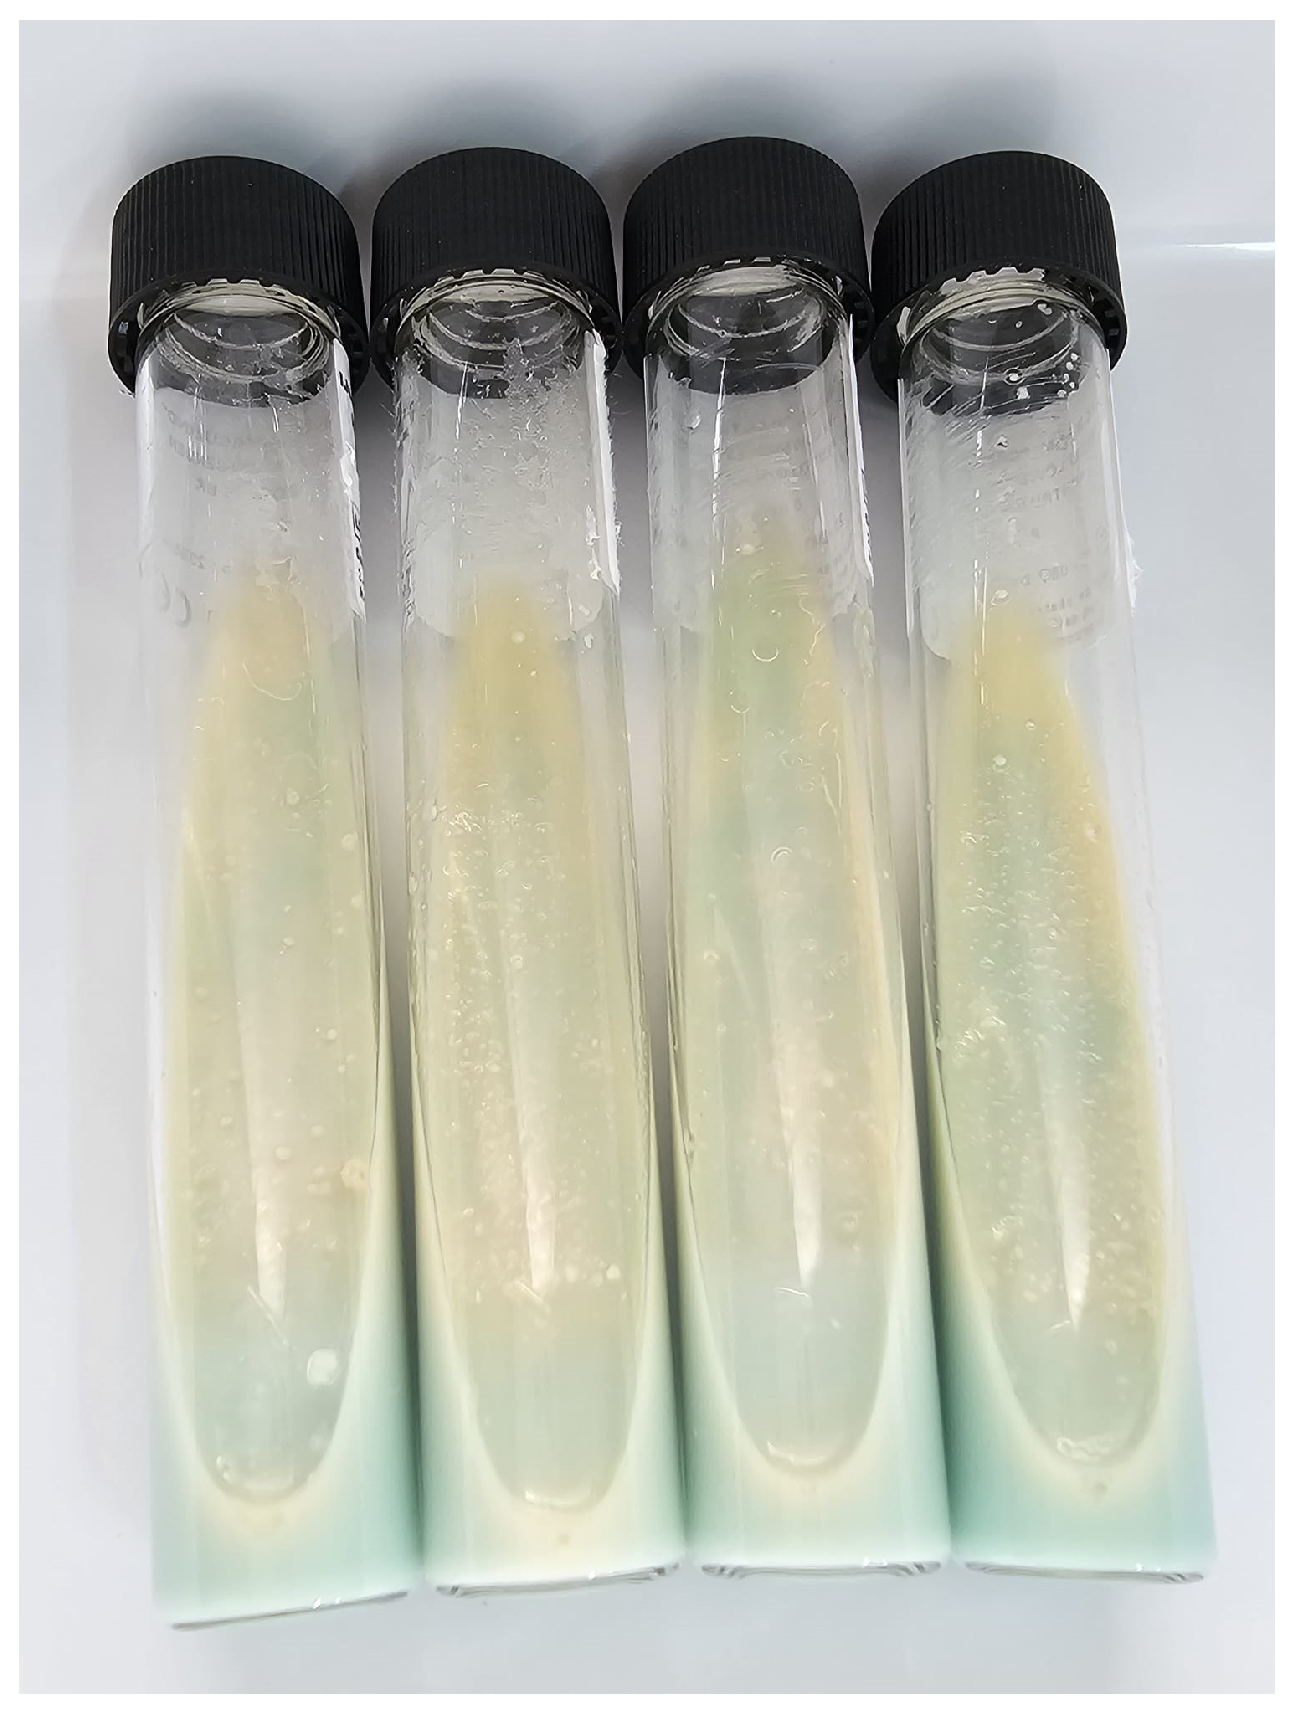

3. Mycobacterial Culture in TB Diagnosis

3.1. Lowenstein–Jensen Method (LJ)